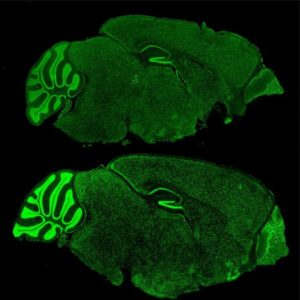

Fragile X Syndrome (bottom) in mouse brains are unable to regulate proteins like Brd4 (green). Credit: Rockefeller University.

In this study, they found that even in an absence of FMRP, the mice were still experiencing abnormal gene expression and changes in chromatin regulation throughout, leading to the conclusion that there was still a mechanism that was transmitting signals to restructure chromatin. Korb then shifted to examining the chromatin reading protein BRD4, which is a protein targeted by FRMP and a known protein associated with tumor growth.

The research team created cells that contained no FMRP gene and confirmed that its absence resulted in definite epigenetic misregulation. Korb and her colleagues then moved to a drug popular in cancer treatment that inhibits BRD4, and determined that the inhibition of BRD4 was effective in reversing the over-production of synapse proteins, which was an impressive find for Korb.

“The results were exciting,” she said. “In cellular and animal models of Fragile X Syndrome, we saw a return to normal numbers of neuronal synapses and a decrease in behavioral symptoms.”